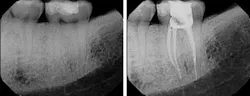

When we talk about three-dimensional obturation, various thermoplastic techniques come to mind. Studies have shown that thermoplasticized gutta-percha obturation results in a larger volume of gutta-percha in the canal compared to cold lateral and vertical condensation and obviously single-point obturation. The higher volume of gutta-percha has been taken as proof of a superior seal when, in fact, the seal is dependent upon the intimate relationship of the cement to both the gutta-percha and the canal walls. Consequently, the inference of a higher volume of gutta-percha being proof of a superior seal is secondary to the fact that the cement is forced into a more intimate relationship with the canal walls.

Thermoplastic obturation takes several different forms. Carrier-based thermoplastic systems have evolved away from metal and plastic carriers to the point where they are now constructed of two different phases of gutta-percha, with the outer layer thermoplasticized far more than the inner core, which acts as the carrier. All thermoplastic techniques require the minimum placement of cement, because the coronal pathway for the release of excess cement is occluded first, eliminating the escape valve when room temperature systems are employed. Another thermoplastic approach is the use of a heated spreader that first requires the placement of a conventional gutta-percha point to the constriction followed by heated vertical condensation within 5 mm of the apex and conventional condensation within 2 mm of the apex. This form of thermoplastic obturation adapts the gutta-percha to the walls of the canal within the last 2-3 mm of the canal. Interestingly, the gutta-percha that was placed at room temperature is not affected by the heat introduced by the spreader and remains more or less in the same position as when it was originally placed. Strictly speaking, the most apical placement of the gutta-percha has not been thermoplasticized and is essentially a single-point fill. The advantage is no shrinkage.